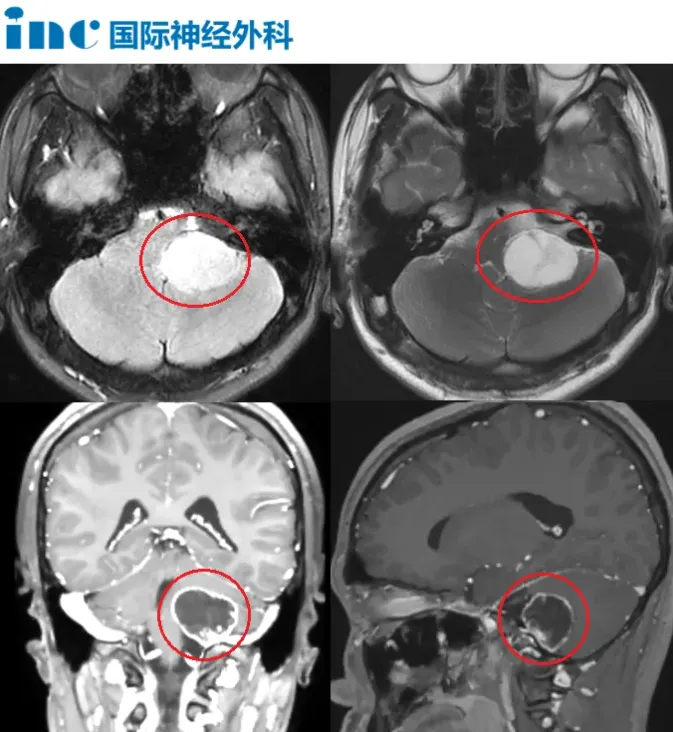

这一查,才揪出了藏在暗处的"元凶"——在颅脑深部一个叫做"颈静脉孔区"的狭窄空间里,长了一颗体积不小的肿瘤。

颈静脉孔区位于颅底深处,解剖结构极为繁杂。这里既是后组颅神经、脑干、颈内动静脉汇聚通行的要道,也是公认的手术高风险区域。一旦在手术中造成损伤,轻则出现声音嘶哑、吞咽困难,重则危及患者生命。

而小凯的肿瘤,偏偏就长在这个"兵家必争"的危险地带。

2024年6月,巴教授中国行示范手术期间,小凯的手术如约进行。显微镜下,教授如同一位精密的"拆弹专家",在全程保护脑干、后组颅神经及重要血管的前提下,将肿瘤一点点剥离,最终实现全切。

当巴教授走出手术室,带来"肿瘤全切、无任何残留"的消息时,小凯的妈妈终于忍不住红了眼眶。术后影像显示:填补骨缺损所用的脂肪组织位置准确,脑干与小脑均获得完全减压——这意味着,最险的那一关,闯过来了。